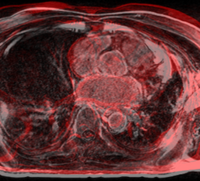

Meningiomasim iter1.jpg

Tumor Simulation for Validating Change Tracking Applications

Determining extent of pathology as it changes over time is an important clinical task. However, there is a lack of a reliable, objective ground truth for evaluating automatic tracking methods. We have developed a simulation tool that can generate MR images with known tumor and edema. More...